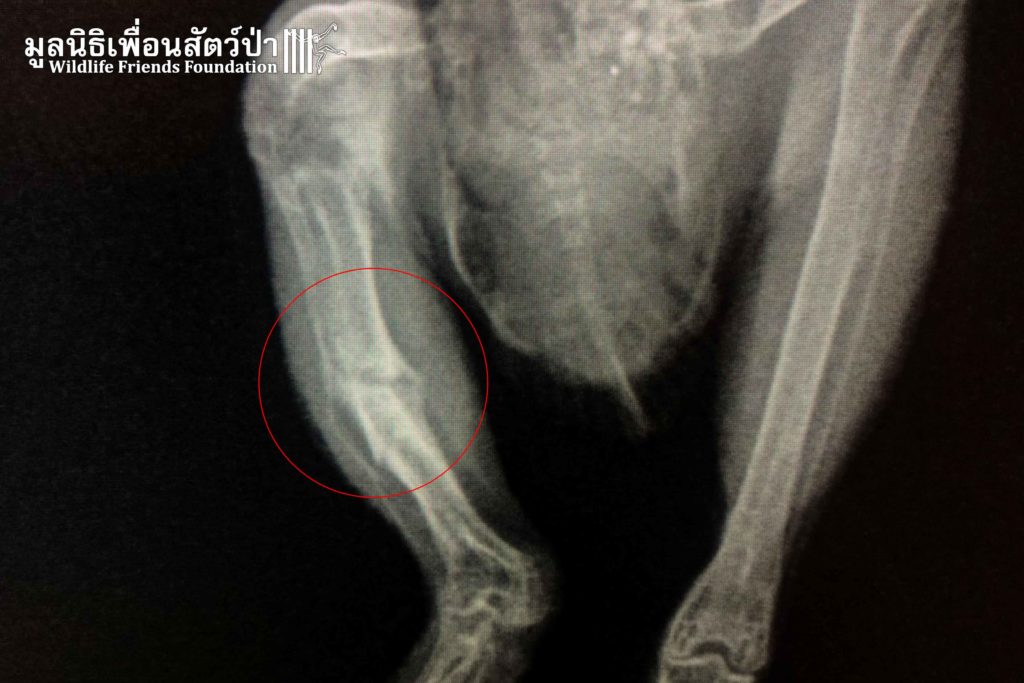

“Hedwig” an Asian barred owlet (Taenioglaux cuculoides) was found by the side of a busy road after being hit by a car. Luckily a concerned local found it and contacted WFFT for help. An X-ray examination showed a bone fracture on the right leg, which is not so severe so this has a good chance of healing. Hedwig will receive round the clock care from our vet team until the bone healed before it can be released.